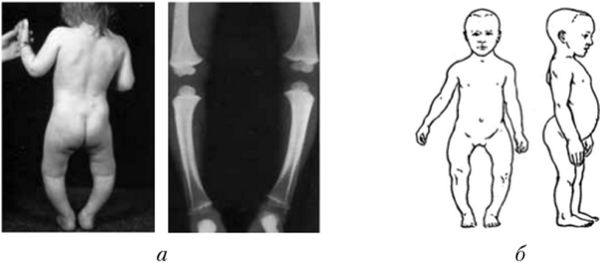

Рис. 7.23. Изменение скелета при рахите:

а — искривление ног; б — деформация черепа, позвоночника, грудной клетки

ний формирования скелета (рис. 7.23, 7.24), что в свою очередь отражается на функциях внутренних органов. По состоянию костной системы детей и подростков можно судить об их физическом развитии.